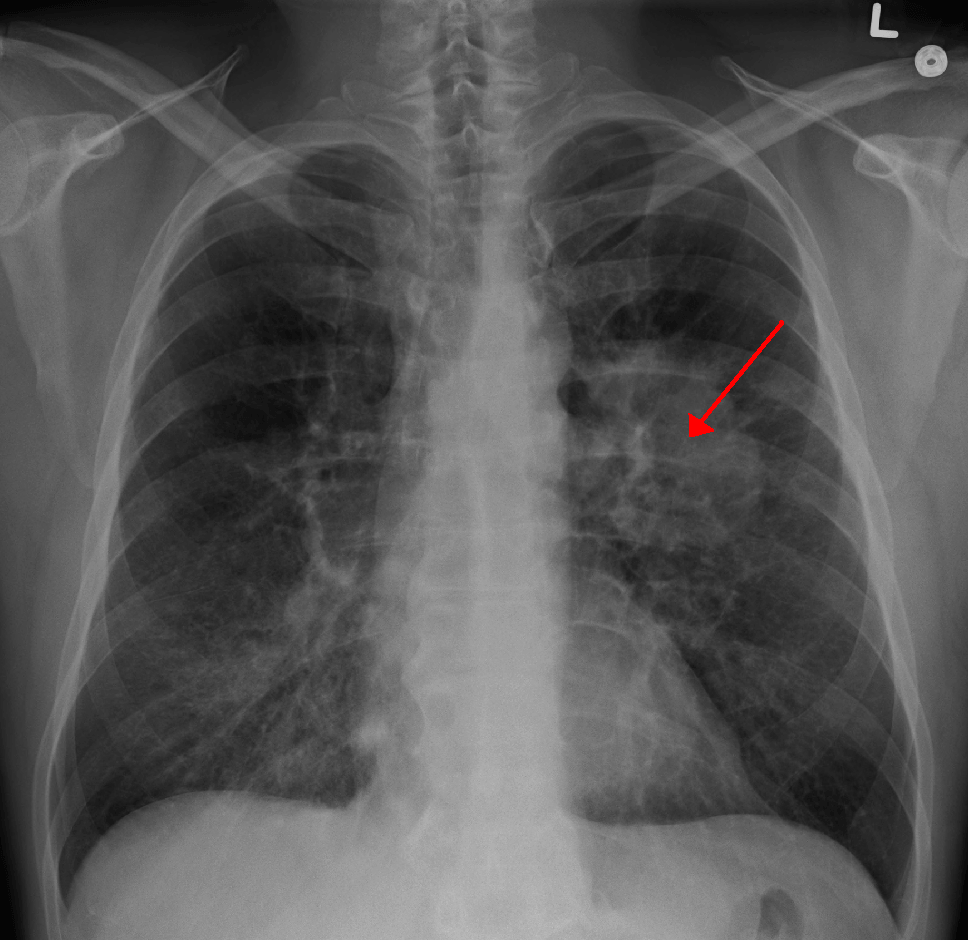

O nemoci se dozvěděla náhodou - požár ji zachránil život

Operace přišla v nejbližším možném termínu

Nemoc byla naštěstí odhalena včas